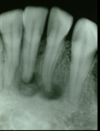

lateral obliques

OPG